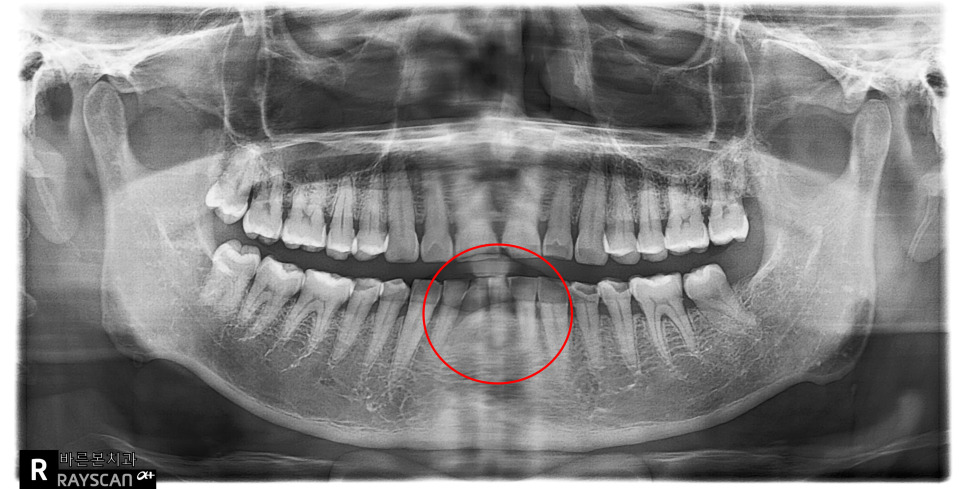

24.02.01(초진) – 69y 김OO님

” 예전에 넘어지면서 다쳤던 치아인데

앞니통증이 너무 심해요 “ 라고 말씀하시며

매탄동치과로 내원하신

환자분의 x-ray 사진입니다.

빨강색동그라미 부위입니다.